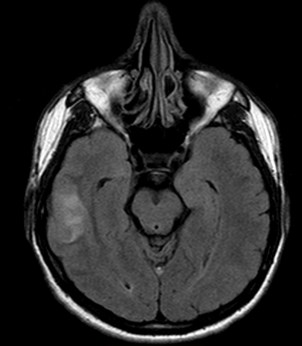

Se decide realizar una RM y una venografía RM para descartar una TVC. Ante el mal estado de la paciente, la cual no colabora, solo se puede terminar realizando secuencias FLAIR y Difusión.

El protocolo de estudio debe incluir secuencias FLAIR, T1(con y sin contraste), T2, y T2*, así como secuencias de difusión (DRM) y venográficas.

Secuencias convencionales de RM:

- Signos directos: Señal hiperintensa del seno trombosado en T1, que indica la ausencia de flujo y la presencia de material trombosado. Un falso positivo sería la señal hiperintensa por éstasis sanguíneo; para solucionarlo usar estudio contrastado y ver el delta vacío u obtener secuencias en diferentes planos del espacio. Por otra parte, el trombo, al igual que la sangre, presenta cambios en su evolución. En fase hiperaguda, será isodenso con respecto al LCR y por tanto es difícil valorarlo. Para solucionarlo, podemos usar secuencias T1 con contraste y ver el «stop» del flujo o usar secuencias T2 gradiente, ya que es muy sensible a la desoxihemoglobina que contiene el trombos fresco.

- Estadio 3: Moderado edema y mayor aumento de PIC. Leve aumento de señal parenquimatosa en T2 ponderado y FLAIR.